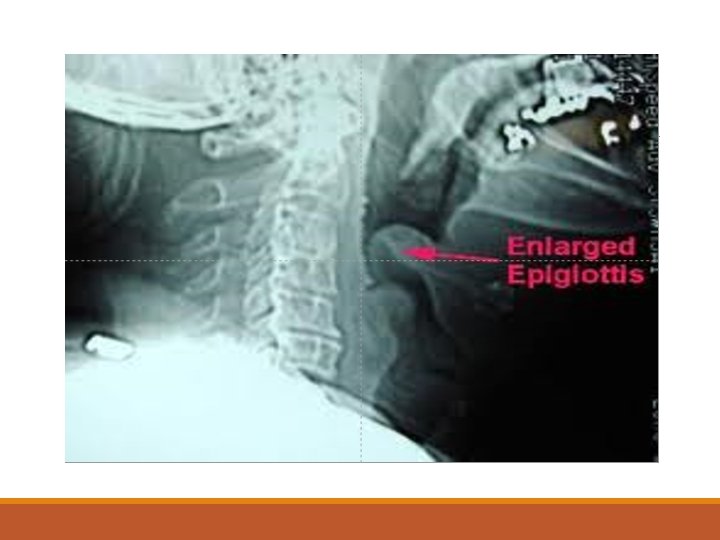

Akut Epiglottit Seyrek görülen ancak yaşamı tehdit eden bir tablo 1 -6 yaş arasındaki çocuklar H. influenzae tip B Viral kruptakinin tersine öksürük yok ya da çok az Ateş çok yüksek, toksik bir görünüm

Akut Epiglottit ØÇocuk hava yollarını açık tutmak için hareketsiz pozisyonda ağzı açık şekilde oturur. Salya akması görülür

Akut Epiglottit ØDil basacağı ile ağız muayenesi çok tehlikeli olup solunum yollarında tam obstrüksiyonu ve ölüme neden olabilir. ØHastalar hemen hospitalize edilmeli, entübasyon yapılmalı ve antibiyoterapi başlanmalıdır. ØBazen de trakeostomi yapmak gerekebilir.